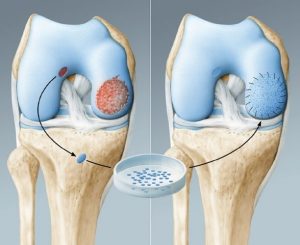

Η συνεχώς εξελισσόμενη έρευνα στο πεδίο των χόνδρινων βλαβών έχει δώσει και τεχνικές στηριζόμενες στα χονδροκύτταρα. Από την άρθρωση του ασθενούς λαμβάνεται υγιής ιστός από τον οποίο απομονώνονται κύτταρα, που στη συνέχεια μπαίνουν σε συνθετικές μεμβράνες κολλαγόνου ή υαολουρονικού ώστε να τοποθετηθούν στην περιοχή της βλάβης προκειμένου να αναπτυχθεί νέος χόνδρος.

Με ανάλογο τρόπο απομονώνονται και τοποθετούνται βλαστοκύτταρα που λαμβάνονται από τον ίδιο τον ασθενή – εναλλακτική και πολλά υποσχόμενη μέθοδος αποκατάστασης είναι και με μεσεγχυματικά κύτταρα. Η τεχνική της αυτόλογης μεταμόσχευσης επιλέγεται για μεγάλες βλάβες, ενώ αποτελεί λύση σε περιπτώσεις ασθενών στους οποίους έχουν αποτύχει άλλες τεχνικές